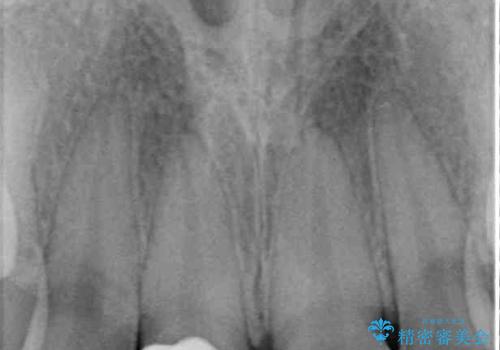

転倒などの強い力がかかった歯は、歯の内部の歯髄組織が壊死してしまったり、外部吸収と知って、歯根の一部が吸収してしまったりと、思わぬ問題を抱えていることがあります。

治療期間においてはこのようなトラブルは発生していませんでしたが、今後も定期的にレントゲン写真撮影などで経過を見ていく必要があります。